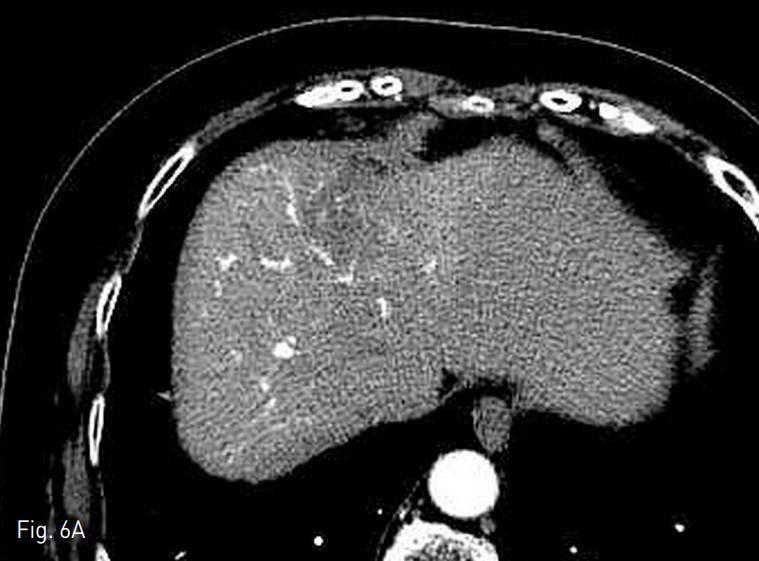

Fig. 6. Computed tomography obtained at 11 months after transarterial radioembolization.

A. Main tumor size is decreased from 7.5cm to 1.8cm.

환자는 시술 후 8주 이상 호흡기나 위장관의 증상 발생하지 않았고, 간기능 검사의 큰 변화는 없었으며, 이후 추적 검사에서 지속적인 종양 크기 감소 및 간문맥 종양혈전증의 감소를 보였다 (Fig. 6)

가장 큰 종양은 시술 후 11개월째 장경 7.5cm에서 1.8cm으로 감소하였고, modified Response Evaluation Criteria in Solid Tumors (mRECIST)에 따른 partial response를 보였다. 종양 표지자는 시술 전 AFP 259.0ng/ml, PIVKA-Ⅱ 6520mAU/ml에서 시술 후 11개월째 각각 9.4ng/ml, 31mAU/ml로 감소하였다.